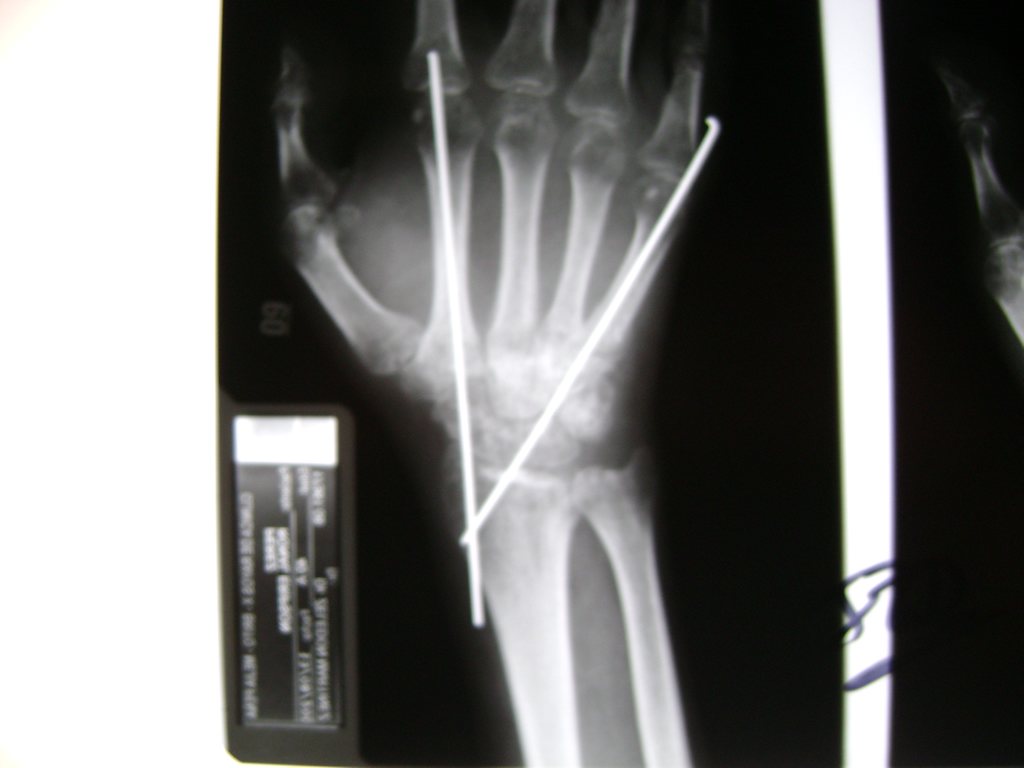

Cirugías de Calcaneo - Cirugías de Muñecas y Manos

Los procedimientos más comunes en cirugía de la mano son aquellos destinados a reparar traumatismos, incluyendo lesiones de tendones, nervios, vasos sanguíneos, y articulaciones; huesos fracturados; y quemaduras, cortes, y otros daños de la piel.